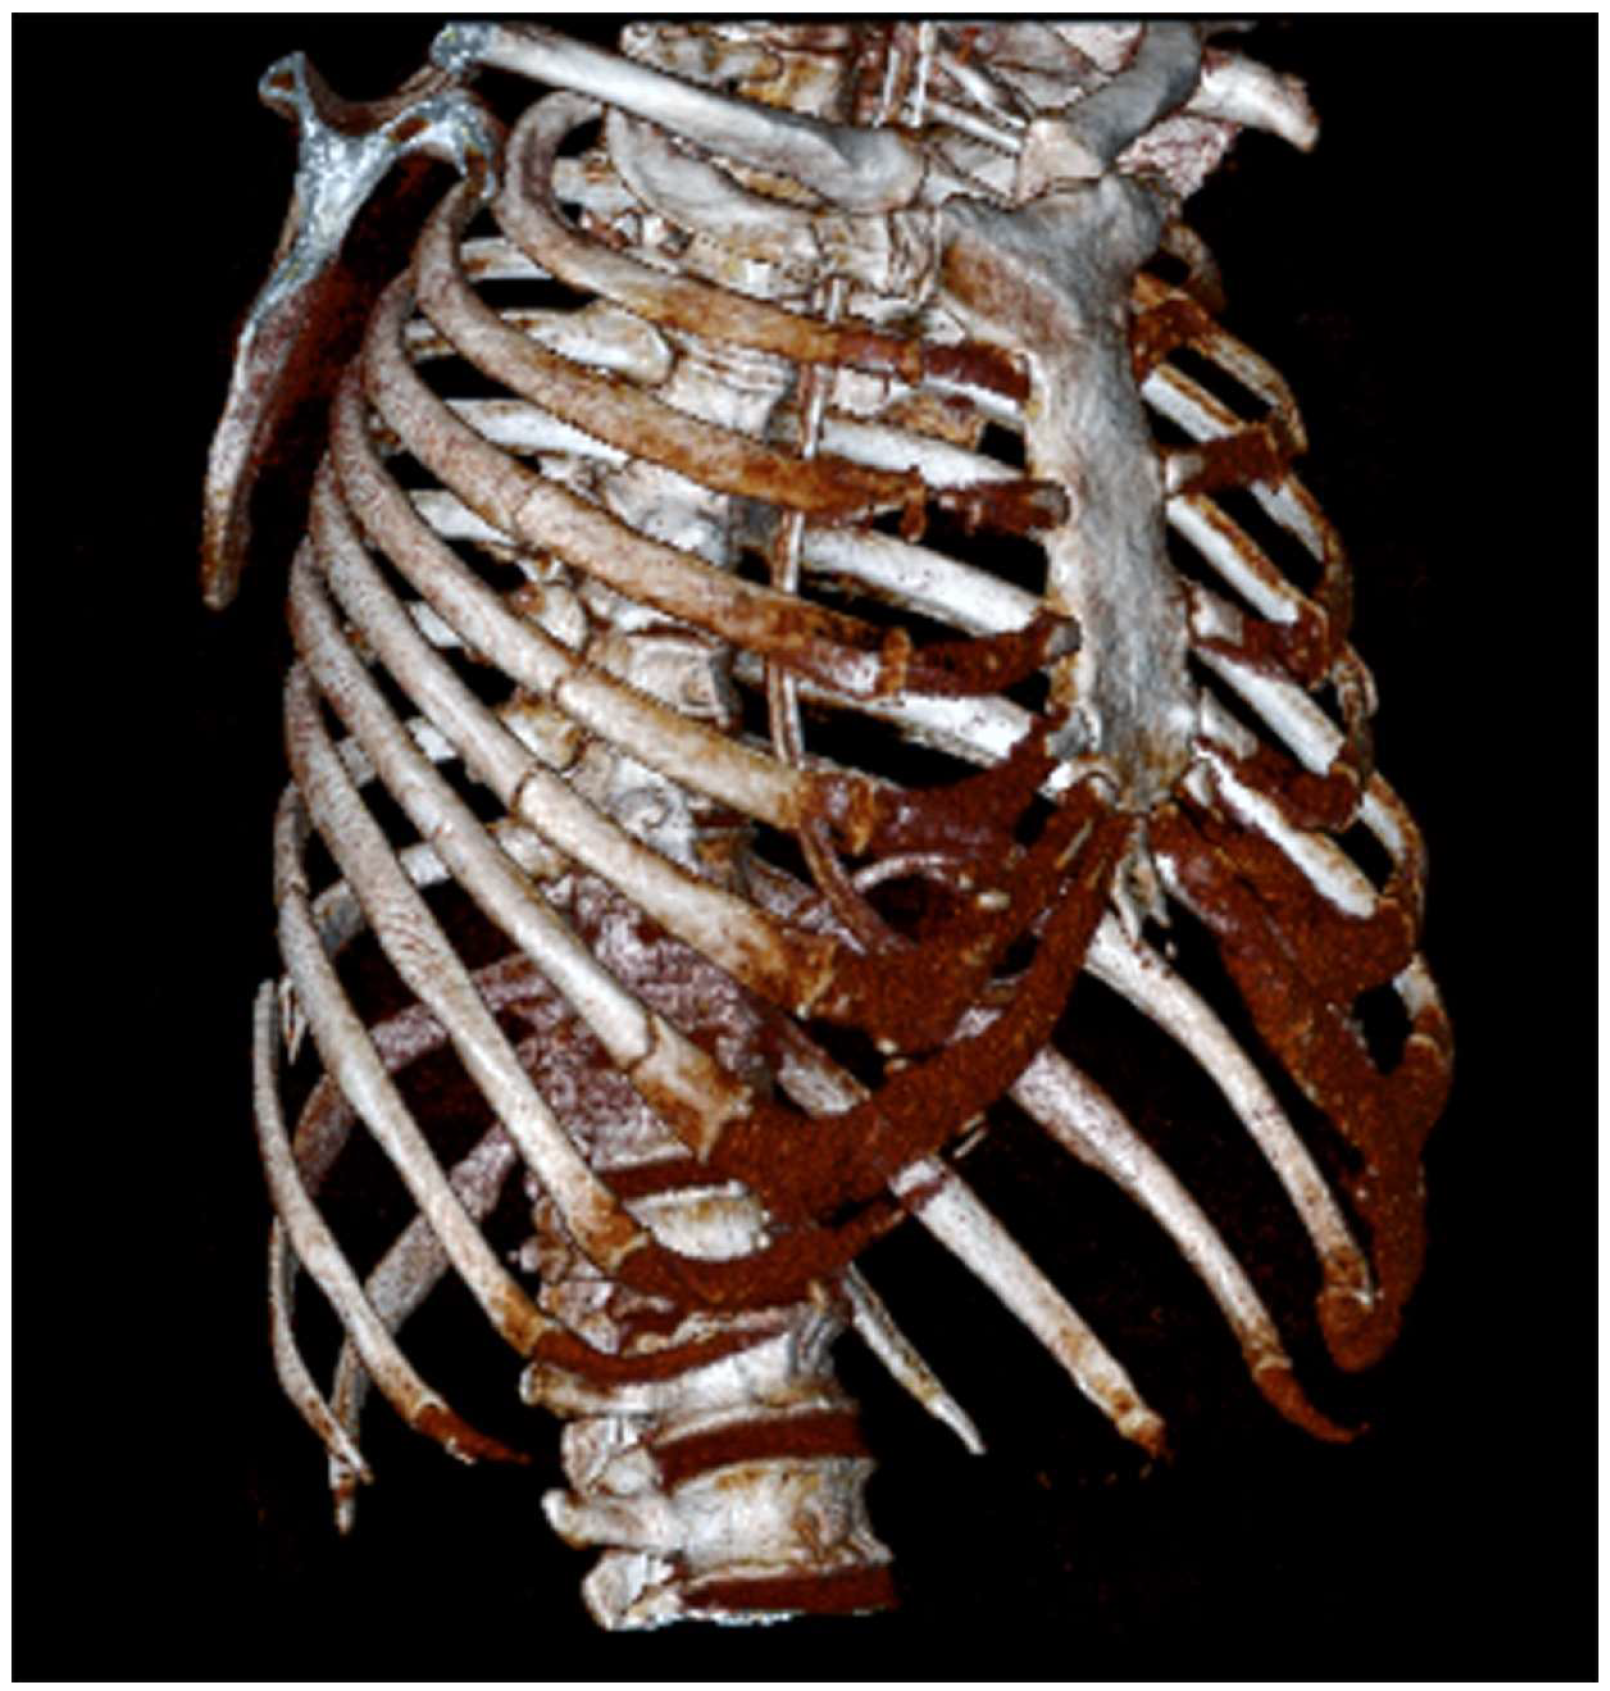

Bilateral Serratus Plane Block in a Critically Ill, Mechanically Ventilated Patient with Multiple Rib Fractures Due to Severe Thoracic Trauma: Case Report and Literature Review

3.1. Case Presentation